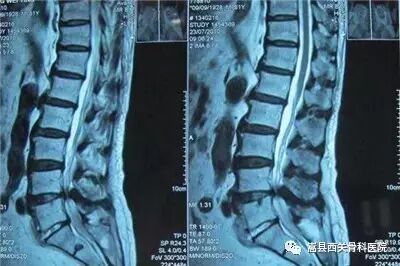

腰椎管狭窄影像资料

腰椎间盘的退变,椎体的骨质增生,后方小关节突的增生,黄韧带的肥厚,椎体滑脱都是造成椎管狭窄的主要原因!

椎体滑脱导致椎管狭窄,术后完全复位,椎管狭窄解除!